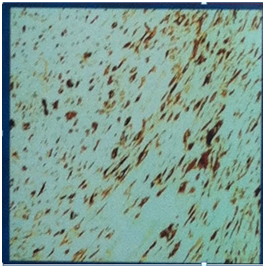

During the endoscopy of the larynx was found a large mass arising from the right vocal cord, causing significant obstruction of the glottis (Figure 1).

Figure 1 Endoscopic view of the laryngeal tumor, preop.